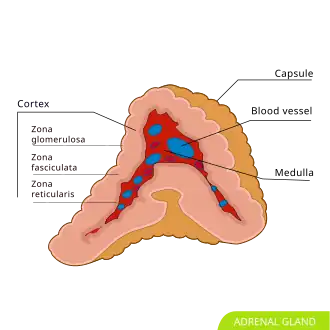

Adrenal gland with medulla in the middle | |

The adrenal medulla (Latin: medulla glandulae suprarenalis) is the inner part of the adrenal gland.[1] It is located at the center of the gland, being surrounded by the adrenal cortex.[1] It is the innermost part of the adrenal gland, consisting of chromaffin cells that secrete catecholamines, including epinephrine (adrenaline), norepinephrine (noradrenaline), and a small amount of dopamine, in response to stimulation by sympathetic preganglionic neurons.[1][2]

The adrenal medulla consists of irregularly shaped cells grouped around blood vessels. These cells are intimately connected with the sympathetic division of the autonomic nervous system (ANS). These adrenal medullary cells are modified postganglionic neurons, and preganglionic autonomic nerve fibers lead to them directly from the central nervous system. The adrenal medulla affects energy availability, heart rate, and basal metabolic rate. Recent research indicates that the adrenal medulla may receive input from higher-order cognitive centers in the prefrontal cortex as well as the sensory and motor cortices, providing credence to the idea that there are psychosomatic illnesses.[3]